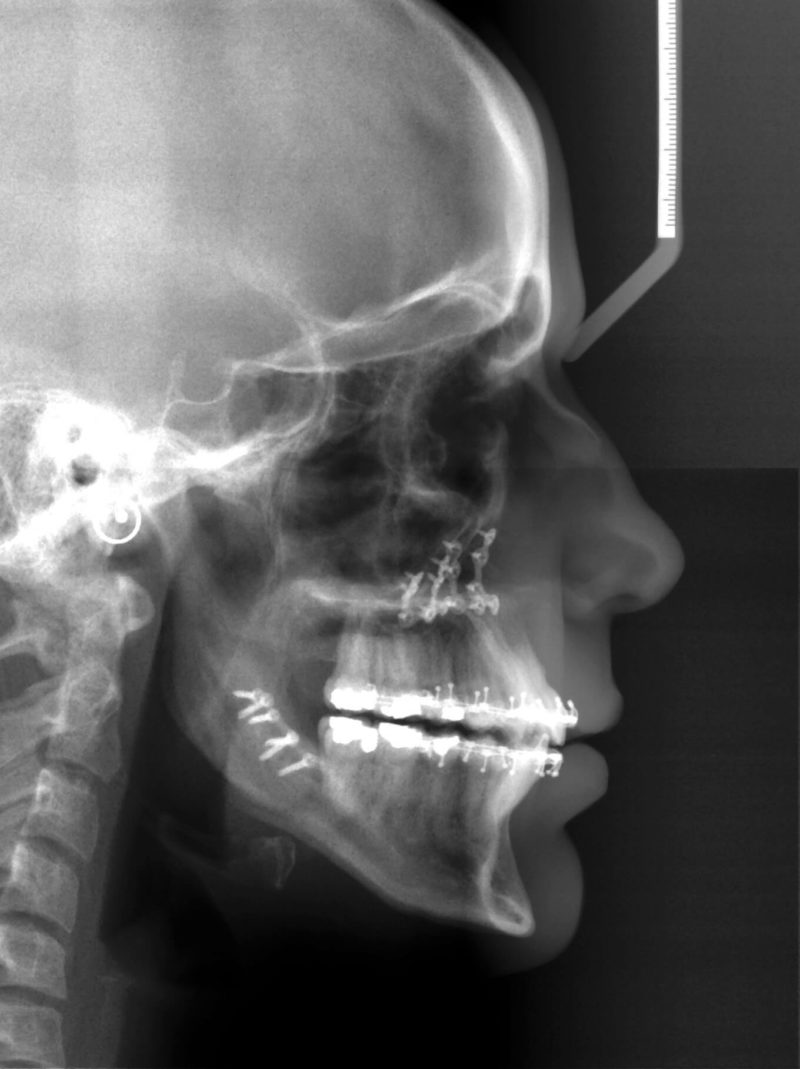

From yangorthodontics.com

One of our patients at Yang Orthodontics had a severe underbite Orthodontics And Orthognathic Jaw Surgery The length of your actual surgery is approximately two to three hours per jaw. Jaw surgery, also called orthognathic surgery, is surgery that helps align your upper jaw (maxilla) and lower jaw (mandible). A guide for patients considering orthodontics and jaw surgery (orthognathic treatment). They may include orthognathic, which refers to the causes and treatment of bones. Orthognathic surgery is. Orthodontics And Orthognathic Jaw Surgery.